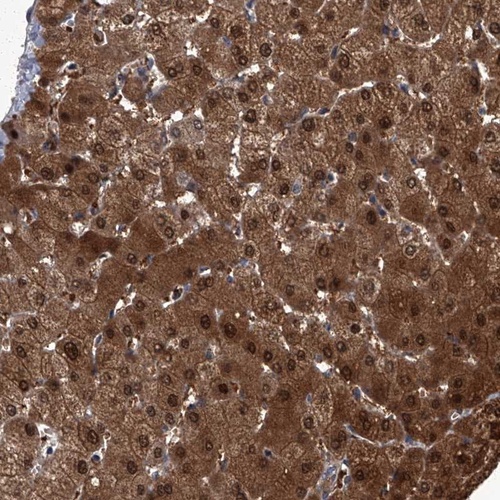

Immunohistochemical staining of human liver shows strong cytoplasmic and nuclear positivity in hepatocytes.